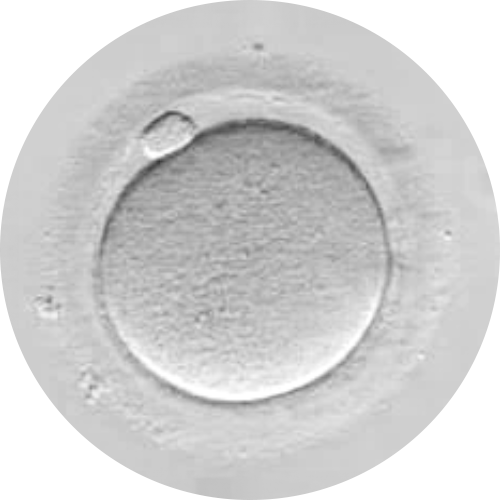

ÓVULO RESTAURADO

ÓVULO CON BAJA CALIDAD OVOCITARIA